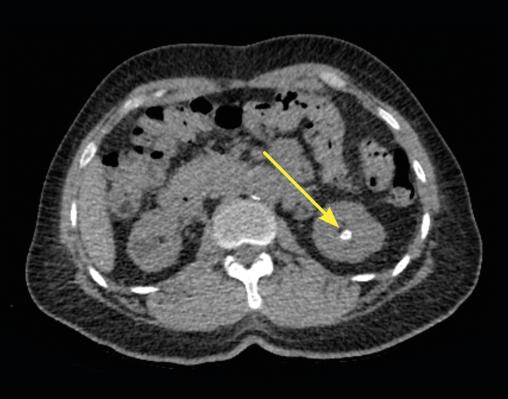

Lors de son hospitalisation, un scanner abdominal permet de localiser avec précision un calcul caliciel rénal radio-opaque gauche de 6 × 8 mm, de faible densité (354 UH), sans dilatation calicielle (fig. 1). En corrélation avec la lecture du scanner, le pourtour du calcul est difficilement visualisé sur la radiographie de l’abdomen sans préparation (fig. 2).